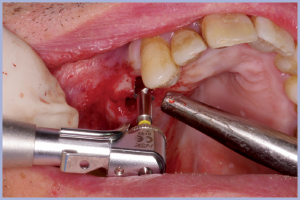

Si realizza la Dima Chirurgica e si programma l’intervento in sedazione cosciente perché il paziente è un soggetto ansioso, con la collaborazione della specialista in anestesia. La sedazione cosciente viene indotta con miscela di gas di protossido di azoto e ossigeno e benzodiazepina a emivita breve (Midazolam) in vena. Con questa tecnica il paziente mantiene i riflessi oro-faringei e risponde ai comandi a seconda dell’esigenza dell’operatore. Si esegue, comunque, l’anestesia locale per infiltrazione con articaina 1:100000, si inserisce la Dima Chirurgica e si esegue lembo mucoso con mucotomo circolare.

In seguito, si esegue la sequenza delle frese chirurgiche con stop e diametri e lunghezza pianificati con sistema Real Patient™ Guide System (3DIEMME® Srl, Cantù (Co)), si inseriscono gli impianti e i tappi di guarigione e si congeda il paziente senza aver eseguito il lembo chirurgico e punti di sutura (Figg. 1-38). I vantaggi della chirurgia guidata flapless sono un edema e dolore post- intervento minori, riduzione dei tempi di guarigione, assenza di riassorbimento osseo dopo esposizione con il lembo e minori disagi per il paziente (riduzione dei controlli, assenza di dieta liquida e assenza di rimozione dei punti di sutura) e per l’operatore (sicuramente riduzione dello stress). Ovviamente non sempre si può eseguire un intervento di chirurgia guidata a cielo coperto; è, infatti, indispensabile avere a disposizione un discreto osso in termini di qualità e quantità . Con questi presupposti il sistema assicura un’ottima predicibilità e la possibilità di effettuare anche un carico immediato con protesi provvisoria.

- Figg. 13-29 – Osteotomia con passaggio di frese per chirurgia guidata a diametro crescente